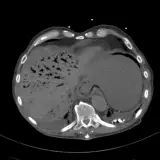

Over 2,100 interactive radiology cases, curated by radiologists for your level of training. Scroll, window, and view cases full screen — just like on PACS. Click linked findings in each writeup to jump straight to them on the image. Cases include sample reports, a focused discussion section, original illustrations, and videos.

完全交互式病例,配备您在 PACS 上期待的各项工具——滚动、调窗、缩放、平移、测量、ROI 和全屏模式。

丰富的标注直接在病例图像上突出关键发现。点击病例讲解中的关联发现,即可跳转至其在扫描上的精确位置。